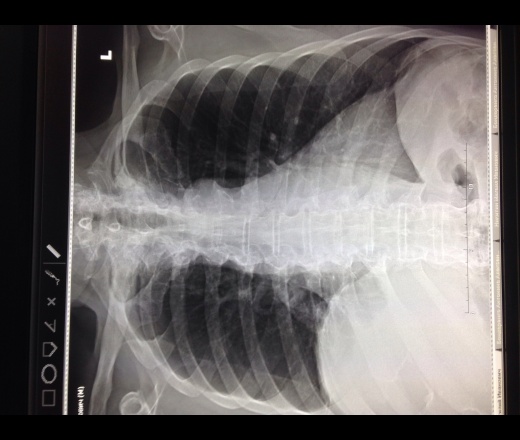

Поделитесь пожалуйста своим мнением! Мужчина 75лет, поступает в приемный покой с температурой 39; повышение АД; ИБС; ХСН; склеры желтые. В н/ отделе справа дыхание не проводится. Просят исключить пневмонию. Смущает высокое стояние правого купола диафрагмы. Думаю, что это за счет увеличенной печени. Нет ли ателектаза S5??

Боком смотреть конечно немного печально ). По мне ателектаза нет, а вот жидкость справа в синусе может быть, я бы порекомендовал УЗИ бр полости и плевральных полостей

Согласна с возможным выпотом, загружайте снимки с компа, с телефона они всегда развернутые

У меня складывается впечатление о правостороннем наддиафрагмальном гидротораксе. Для уточнения диагноза необходимо полипозиционное исследование (например, латерография)

Как пишет коллега NIL, выпот может быть не столько в синусах, сколько над диафрагмой,под основанием легкого и "симулировать" высокое положение диафрагмы. УЗИ обычно в этих случаях помогает оценить количество содержимого.

Йес! Но может ничего не оказаться, а просто высокое стояние правого купола. Даже на КТ. И так бывает

Выпот справа в незначительном количестве, не исключается слева тоже, обычно такое высокое стояние диафрагмы при плеврите обусловлено асцитом - рекомендовала бы УЗИ брюшной полости и плевральных полостей, учитывая клинику

Латерография или УЗИ плевральных полостей раставит все точки. Возможно это особенность этого человека, релаксация диафрагмы тоже так выглядит.

Отметил бы в описании диффузное усиление легочного рисунка, больше выраженное в 9-х сегментах с обеих сторон. Написал бы заключение: вероятный плевральный выпот справа, не исключена двухсторонняя нижнедолевая пневмония. Если нет латероскопа, то - рек. УЗИ плевральных полостей. R-контроль через 3-5 дней.

С учетом клиники у пациента можно предположить пневмонию. Думаю, что у пациента с сердечной недостаточносью, желтыми склерами и температурой 39 гр. просто высокое стояние диафрагмы или её релаксация клинического значения не имеют.

Высокое стояние купола диафрагмы.Какой ригидности должно быть легкое или плотность жидкости чтобы жидкость была над диафрагмой?? ИБС,ХСН дадут гироторакс с малым у.в.ПО узи жидкость м.б.-в синусах,но очень мало 5-10 мм.А температура м. б.от чего угодно.

Коллега, наддиафрагмальный плеврит для меня - не новость. Периодически встречается. Отдифференцировать помогает латерография ( наши УЗИсты не желают этим заниматься, у них свой вал)

Думаю, жидкость над диафрагмой, кстати, не так уж редко встречается. А к вопросу о диагностике все-же напрягла бы УЗИстов.

По снимку может быть высокое стояние купола диафрагмы не исключается наддиафрагмальный выпот.доплнительно латерограмма и узи

Наддиафрагмальный плеврит,конечно,не редкость.Но ,с учетом,повышения АД,ИБС,ХСН мог бы предположить трансудат.Так не случилось,отсюда все вышеизложенное.С уважением МСЧ.